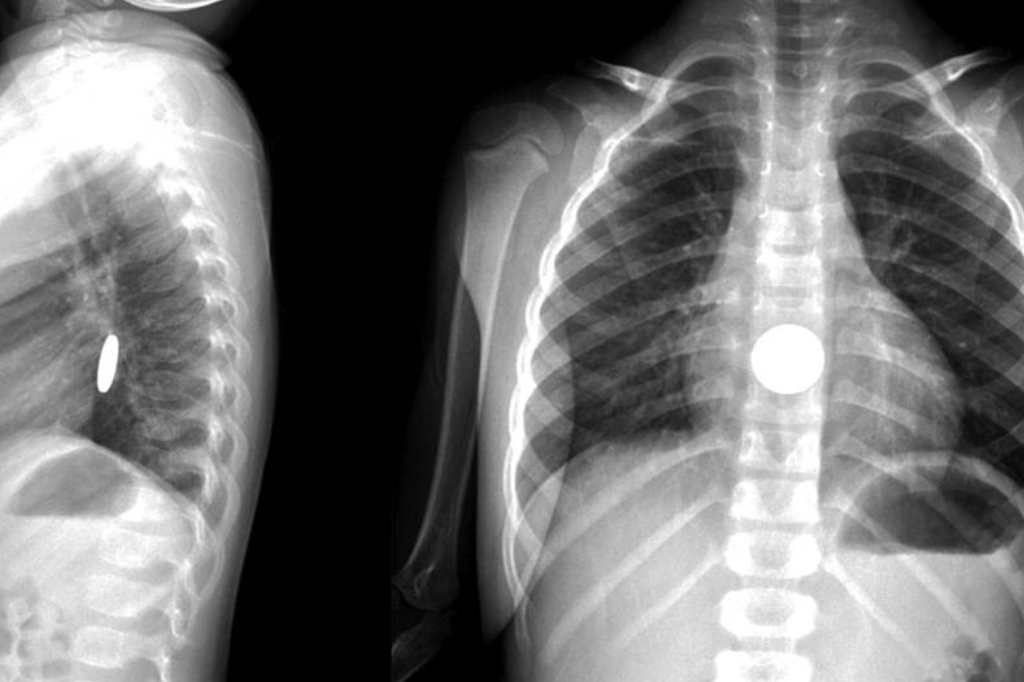

Одна мама из Подмосковья рассказала, что даже не заметила, как её двухлетний сын открыл игрушку и достал из неё батарейку. Ребёнок просто играл рядом, никаких подозрительных звуков или криков не было. Но спустя несколько минут она увидела, что сын внезапно начал сильно пускать слюну и хрипеть, словно подавился и срочно вызвала скорую помощь. Сначала она решила, что это простуда или аллергия. Но педиатр скорой сразу заподозрил химический ожог и отправил малыша на рентген. На снимке была видна та самая «таблетка». Ребёнка экстренно доставили в операционную. Врачи потом сказали: ещё немного — и ожог стал бы необратимым.